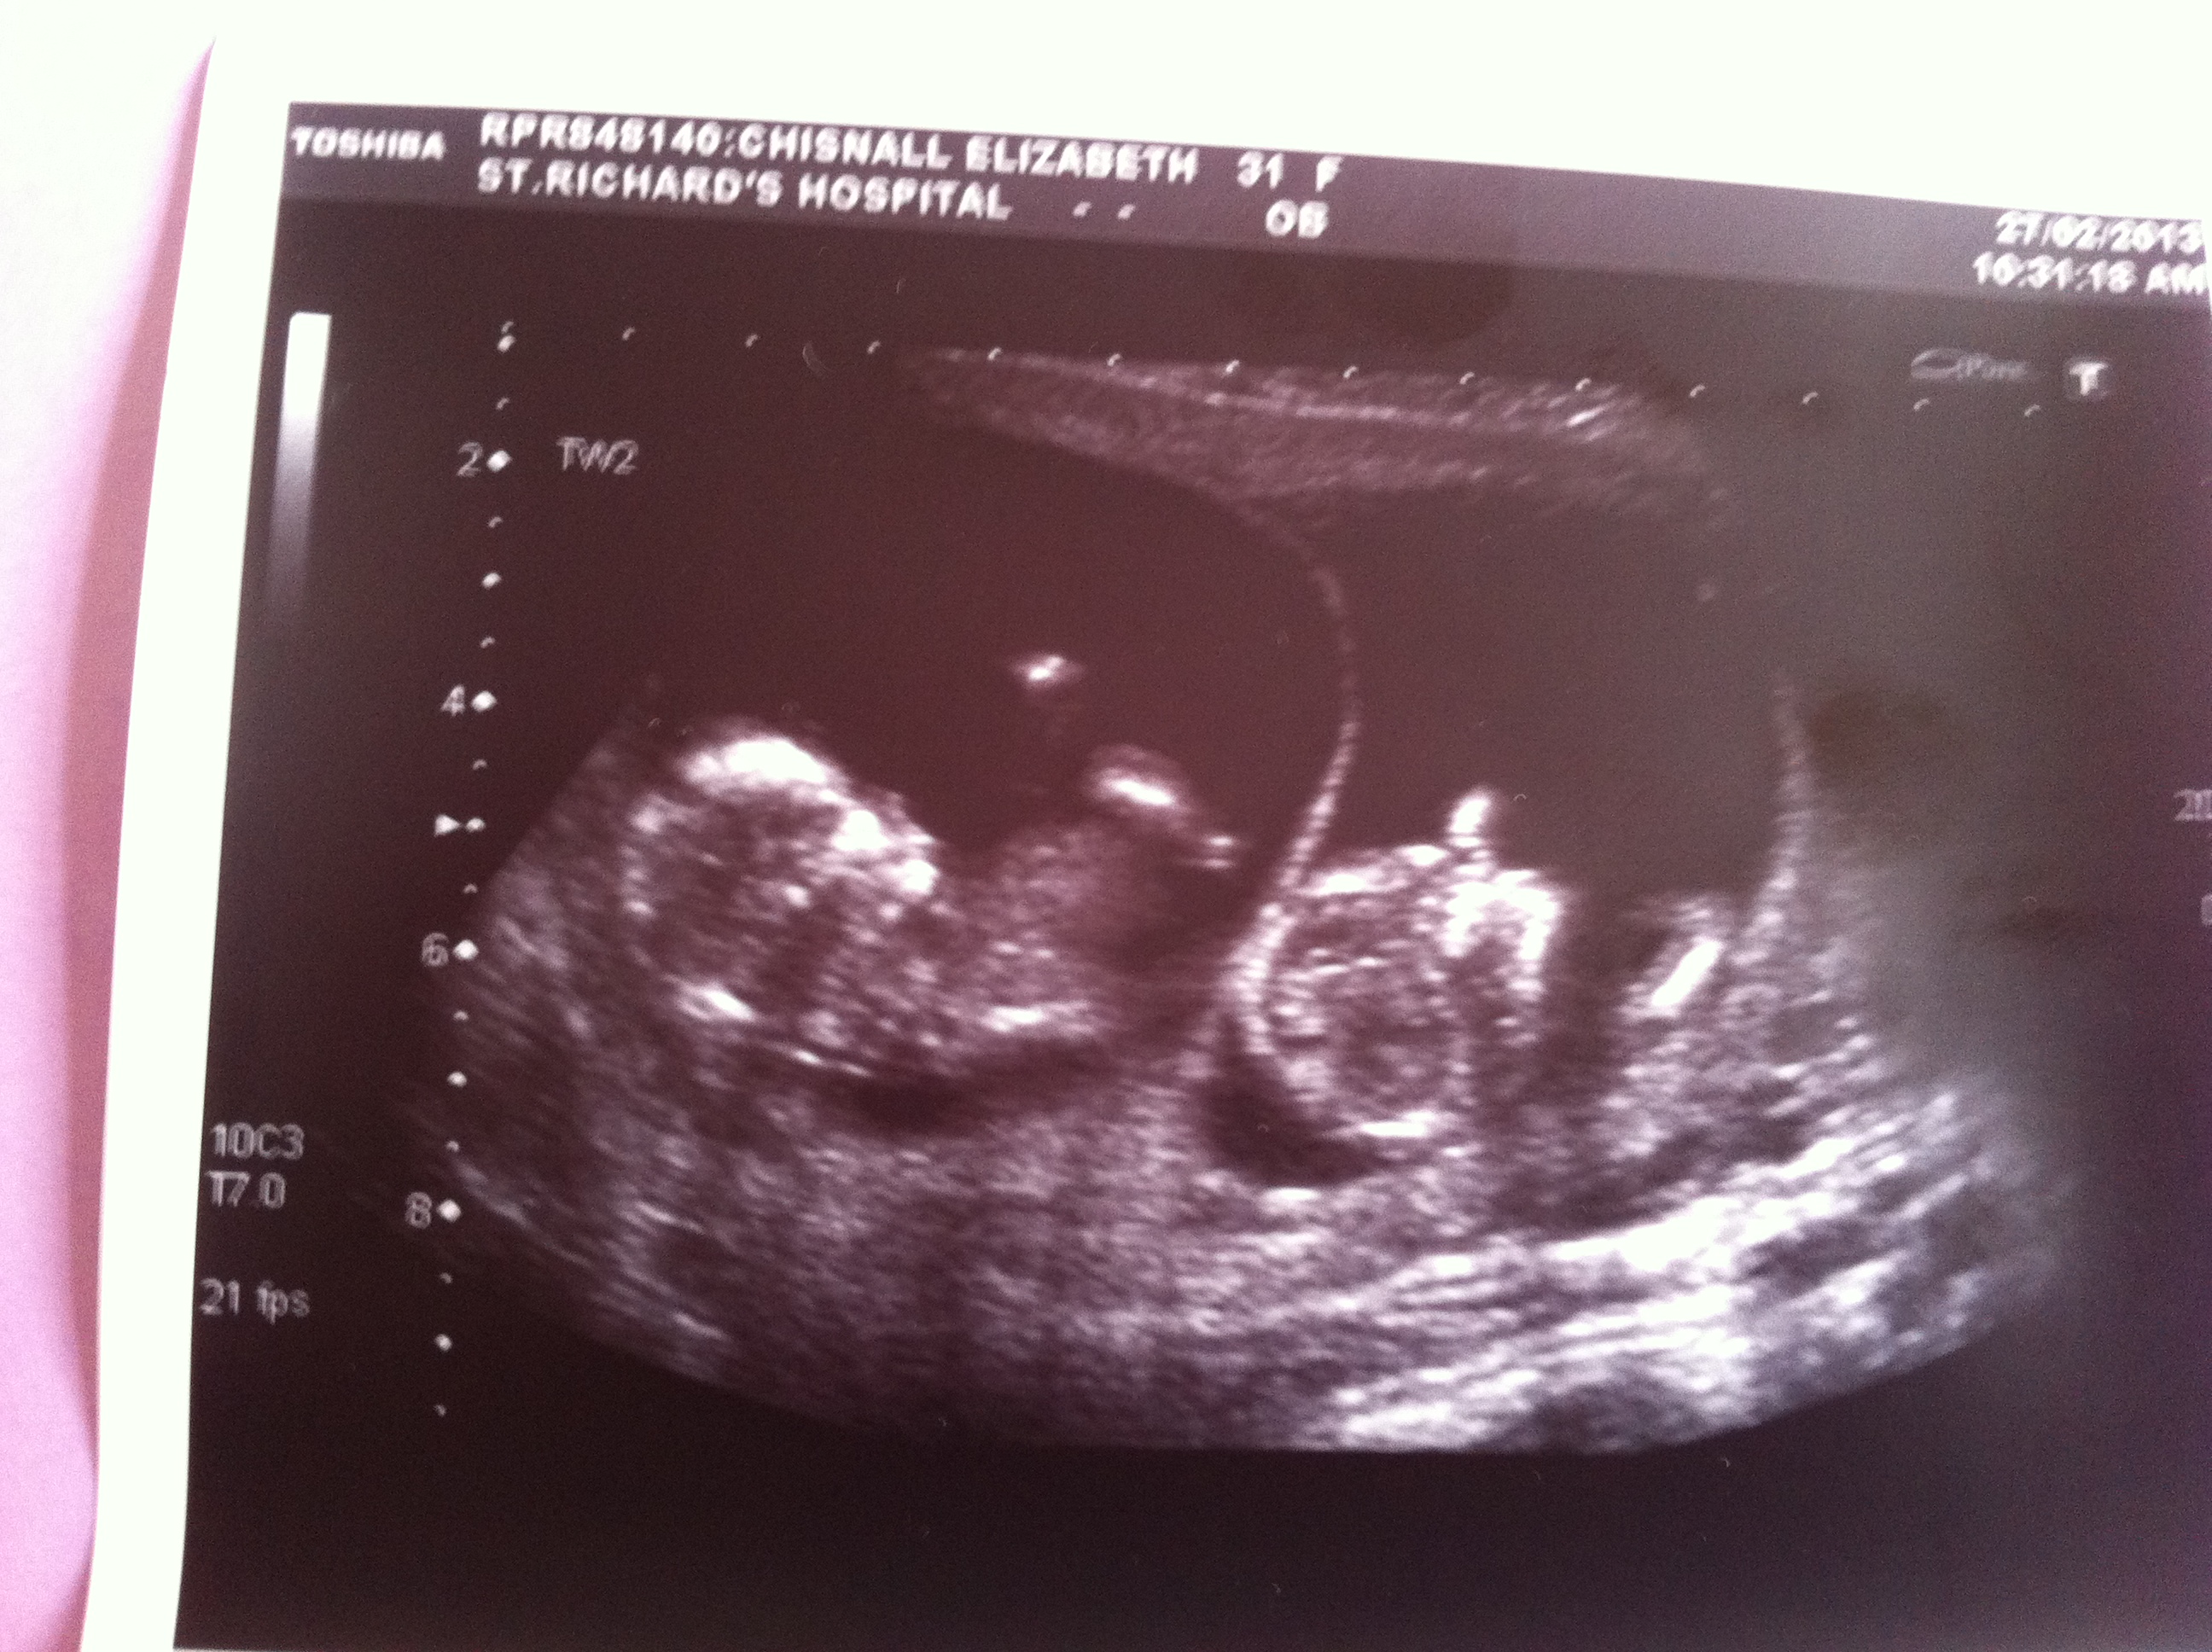

hey so super shock 2 passengers!

don't think any of these are great nub shots but look at them together so cute!

Update sadly twin two only made it to 15 weeks